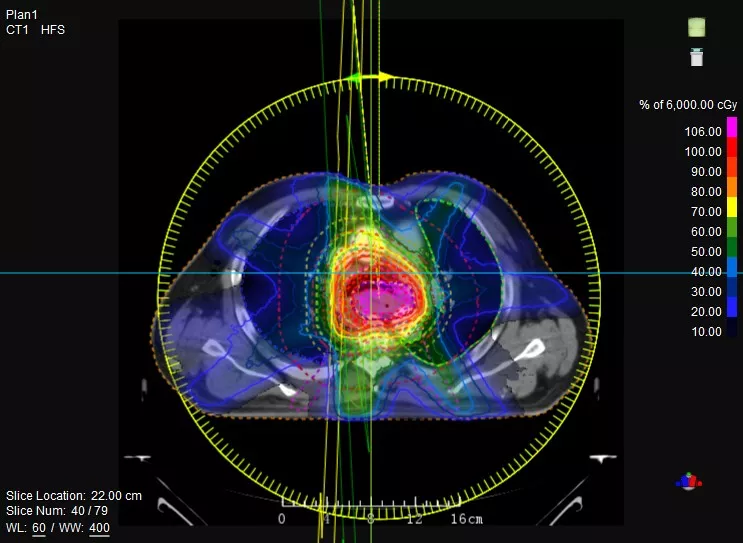

作為Linac與CT一體化融合的尖端放療設(shè)備,聯(lián)影uRT-linac 506c以高清圖像引導(dǎo)提升放療精準度,拓展放療新應(yīng)用,實現(xiàn)精準放療,真正填補國際放療領(lǐng)域空白。

觀其“外在”——首創(chuàng)Linac與CT真正一體化融合,精準CT模擬定位、高清CT影像引導(dǎo),實現(xiàn)精準高效的放射治療。

究其“內(nèi)在”——聯(lián)影自主研發(fā)高劑量率加速管、動態(tài)精準多葉光柵、蒙特卡羅金標準劑量算法、智能勾畫等核心部件與技術(shù),確保系統(tǒng)高兼容性及設(shè)備高效性。

動態(tài)精準多葉光柵,120葉鎢合金葉片,等中心葉片寬度最薄5mm,支持動態(tài)治療

TPS集成蒙特卡羅、三維卷積劑量算法和智能勾畫等功能

一款設(shè)備即可滿足CT模擬定位、CT影像引導(dǎo)、uARC動態(tài)旋轉(zhuǎn)調(diào)強放療等重要臨床應(yīng)用,無需科室/治療室間切換,一站完成放療全流程。